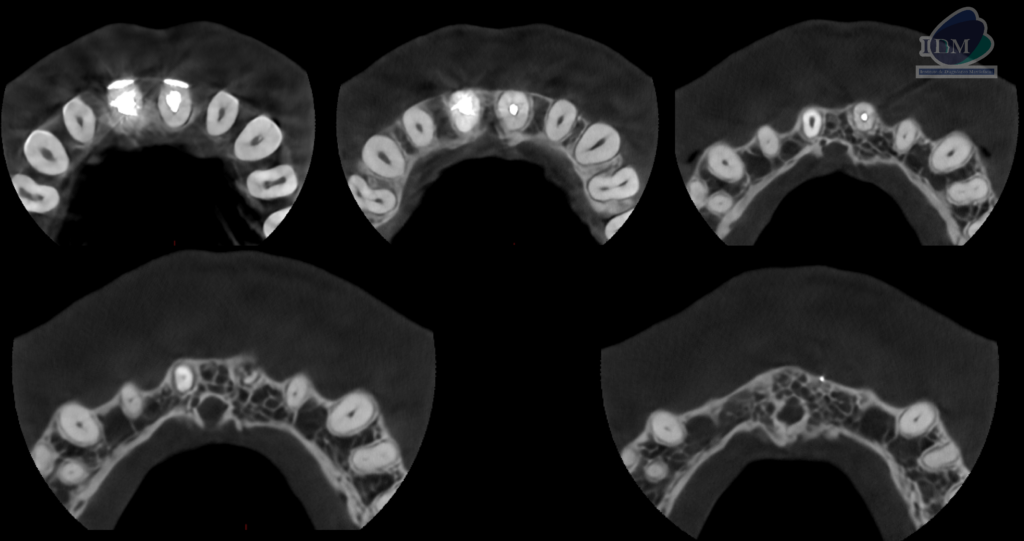

A la evaluación de la tomografía volumétrica (cone beam) en los cortes axiales (Figura 2) y transaxiales (Figura 3) se observa la pieza 11 con obturación parcial de conducto radicular y ensanchamiento del espacio para el ligamento periodontal y pieza 21 con obturación de conducto y reabsorción radicular externa en tercio apical, pérdida de continuidad de la cortical de tabla ósea vestibular. Además, se observa imágenes hiperdensas a nivel de periápice con orientación hacia tabla ósea vestibular de pieza 21 compatible con cuerpo extraño (material de obturación).

CORTES AXIALES